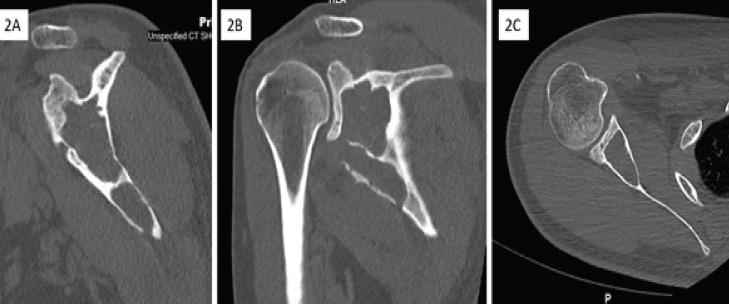

We came across a 30-year-old male farmer with complaints of sero-purulent discharge from a sinus tract wound in the axilla for the past 3 years. He had been previously evaluated elsewhere with blood investigations, pus culture/sensitivity tests, MRI, and CT scans. Blood reports and culture/sensitivity tests were inconclusive and imaging tests were suggestive of a sinus tract originating from the right scapula. He was incorrectly diagnosed as a case of Tuberculosis of the Scapula and started on anti-tubercular medications for 9 months which was ineffective. To confirm the diagnosis, a biopsy was taken from the scapular lesion through a posterior approach. Histological tests revealed a cystic lesion composed of trilaminar membrane consisting of dead and degenerating scolices consistent with "Hydatid Cyst of Bone."

我们遇到一名30岁男性农民,他主诉腋窝处窦道伤口有脓性分泌物,持续了3年。他之前在其他地方接受了血液检查、脓液培养/药敏试验、MRI和CT扫描。血液报告和培养/药敏试验结果不明确,影像学检查提示窦道起源于右肩胛骨。他被错误地诊断为肩胛骨结核,并开始服用抗结核药物9个月,但无效。为了确诊,通过后路对肩胛骨病变进行了活检。组织学检查显示为一个囊性病变,由三层膜组成,内有死亡和退化的头节,符合“骨包虫囊肿”。